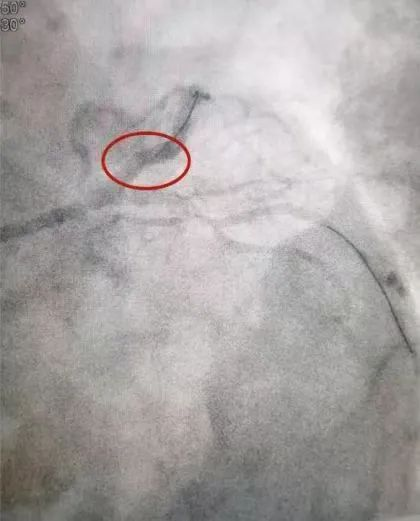

心血管内科是我院的重点专科,我院院长何鹏程也是心血管领域的知名专家,尤其在心血管介入手术方面具有很高的知名度,手术病例多次获邀在国内外顶级学术会议上交流分享。我院在心血管领域方面的实力,吸引众多异地患者前来就医,其中就包括一名来自海南省的患者。林某是一名冠心病患者,曾在海南当地尝试介入治疗开通堵塞的心脏血管但未成功,在海南省心血管同行的举荐下,不远千里专程乘飞机慕名前来我院就医。何鹏程精心准备,带领团队克服了入路血管迂曲、病变血管迂曲、病变血管钙化等冠脉介入手术中的层层挑战,成功为患者开通了前降支病变血管,困扰患者多年的心绞痛症状马上缓解,并很快康复出院。离院之际,林某及其家属对我院的医疗技术和服务水平表达了真心的感谢,表示这趟超越千里的求医之旅达成了他们的期望,取得了良好的效果。

术后:冠状动脉恢复畅通